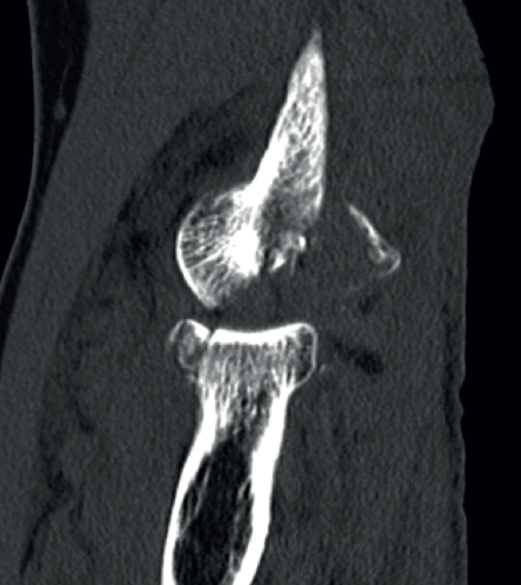

Signos de haber tenido fracturas en la cabeza del radio o la coronoides, aunque ya estén consolidadas, nos ponen en el contexto de un posible antecedente de luxación acompañando a las fracturas. También la presencia de fractura con fragmento cortical posterolateral del húmero, que ha sido considerado como el “Hill-Sachs del codo”(12)(Figura 8).

Y, por supuesto, signos directos, si objetivamos la articulación claramente subluxada (Figura 9).